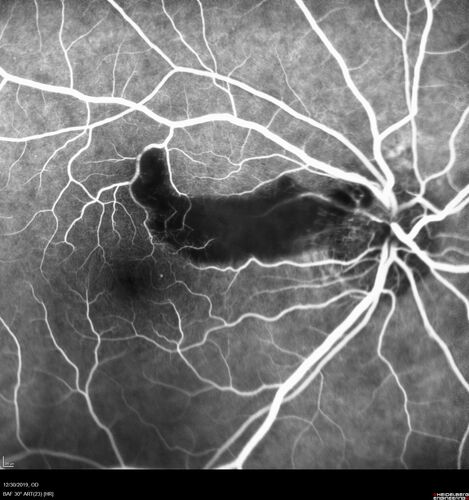

Cilioretinal Artery Occlusion - non central

81 year old female She noticed sudden vision loss in the right eye just before Christmas while watching television.  This was about one week ago.  She noticed when she closed her left eye and looked out of her right eye there was a darkness in the vision.  The left eye is OK.  She has no history of stroke and no neurological problems.  She had a few headaches recently but they went away.

PMHx: HTN, Breast Cancer

Meds: HCTZ, Atorvastatin, Atenolol, Anastrozole

VA 20/80 OD, 20/32 OS

VA improved to 20/40 in one month in the involved eye